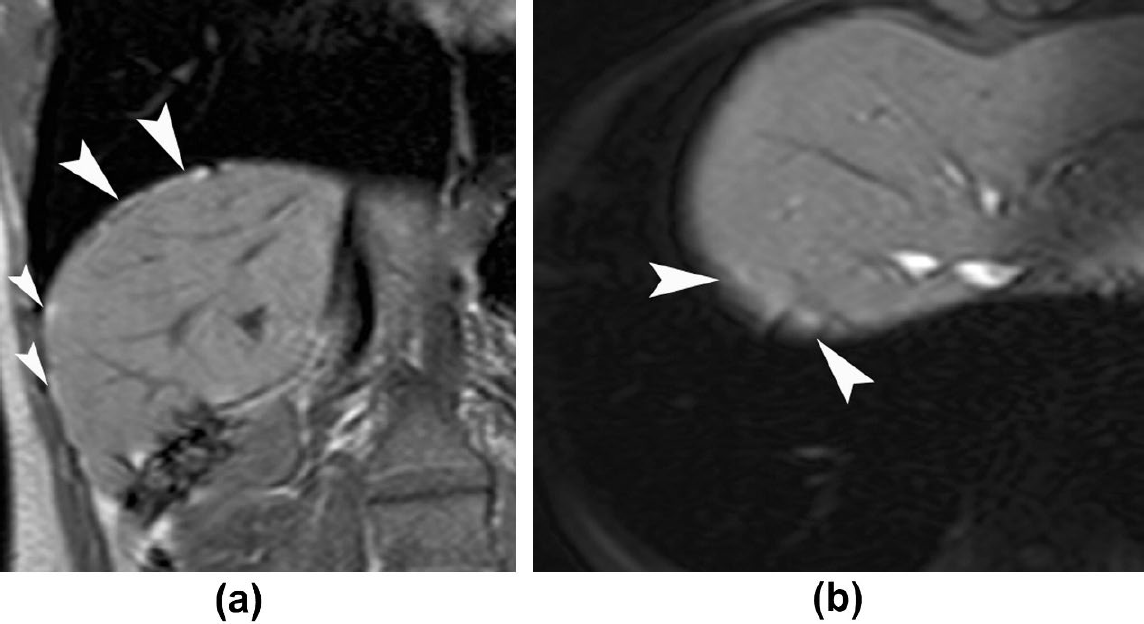

臨床診斷為主,當生育年齡女性有反覆胸痛、氣胸,且與月經週期相關時需高度懷疑。實驗室檢查可能可以發現CA-125上升,但不具有特異性。影像上,胸腔X光可能可以看到橫膈膜上多個小結節(圖三黑色箭頭),其來源是子宮內膜異位造成橫膈膜孔洞,同時肝臟往胸腔突出所造成,在胸腔電腦斷層也可以看到相同特徵(圖四)。對於橫膈膜上的子宮內膜異位,核磁共振有較前兩者高的敏感性及特異性,其在fat-suppressed T1-weighted MRI可以看到訊號增強的病灶(圖五)。最後則是手術的方式,如胸腔鏡手術( video-assisted thoracoscopy, VATS ),直接看到病灶(圖六:橫膈膜結節,圖七:橫膈膜上的子宮內膜),其病理檢驗可看到子宮內膜的間質細胞及腺體。

圖五核磁共振的T1-weighted可以看到訊號增強的病灶

(圖片來源: Thoracic endometriosis syndrome: CT and MRI features Rousset, P. et al. Clinical Radiology, Volume 69, Issue 3, 323 - 330)